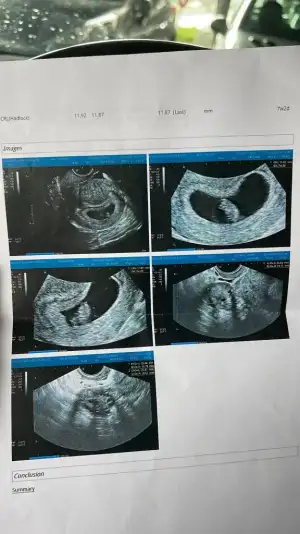

Kaç haftalık burda ilk kese resmi varmı daha küçük olanKızlar keseden cinsiyet tahmini diye birşey varmış atıyorum bakın

Canm anliyorsan bnmkine bakar misjNz ilk ilk kese fotomuz - haftalık karın utrasyonuKaç haftalık burda ilk kese resmi varmı daha küçük olan

Ya yok ben çok anlamıyorum bu ana sagdaysa erkek soldaysa kız kese yuvarlaksa kız fasulye gibiyse erkek diyorlar hep genelde de tutuyorCanm anliyorsan bnmkine bakar misjNz ilk ilk kese fotomuz - haftalık karın utrasyonu

Seninki daha küçük ama keseye ben pek inanmıyorum benim kese resmen fasulye gibiydi erkeek dediler ama benim prensesim olcakKızlar keseden cinsiyet tahmini diye birşey varmış atıyorum bakın

Benimkine de bakarmisiniz rica etsem ikiz gebelik 8. Haftada çekildiSeninki daha küçük ama keseye ben pek inanmıyorum benim kese resmen fasulye gibiydi erkeek dediler ama benim prensesim olcak

Merhaba ilk keseyi atsam tahminde bulunur musunuz :) 5 haftalikKaç haftalık burda ilk kese resmi varmı daha küçük olan

Başka varmı daha belli olan sanki benim oğlumun kesesine benziyor biraz ama içimden de kız geçtiMerhaba ilk keseyi atsam tahminde bulunur musunuz :) 5 haftalik